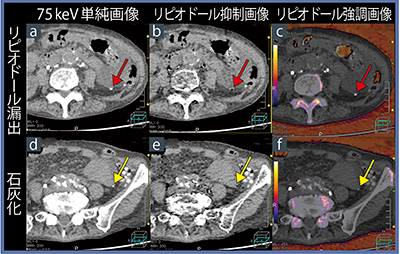

この結果に基づき,実際の症例でもリピオドールの弁別が可能であるかを検討した。症例1は70歳代,女性,腹部大動脈瘤(AAA)術後の乳び腹水症例であるが,リンパ管造影の透視画像や単純CT画像では漏出点を同定できなかった。単純CTのaxial画像では,腹腔内に高吸収体がありリピオドールの漏出が示唆されたが,既存の石灰化も複数あり鑑別が困難であった。そこでDECTを施行し,ヨード造影剤のDE係数を用いて仮想単純CTで解析すると,リピオドールが抑制されて,石灰化が抑制されていない画像が得られた。しかし,リピオドールの抑制は部分的であった。一方,リピオドールのDE係数で解析すると,リピオドールは全体的に抑制され,より高精度のリピオドール弁別が可能であった。さらに,リピオドールの漏出と石灰化を鑑別するために解析すると,リピオドールの漏出が疑われる部位は,抑制画像(図1b↓)では抑制され,強調画像(c↓)では強調されて描出された。一方,石灰化と思われる部位では抑制も強調もされていない(図1d〜f↓)。反対に,石灰化のDE係数で解析すると,リピオドールの漏出部位も抑制されるため,弁別が困難であった。

図1 症例1:AAA術後の乳び腹水のリピオドール弁別解析